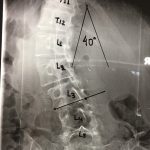

- Μετεγχειρητικές ακτινογραφίες

Εικ. 4 Μετεγχειρητικές ακτινογραφίες: Παρατηρείται σημαντικοτάτη διόρθωση της σκολιωτικής παραμόρφωσης.